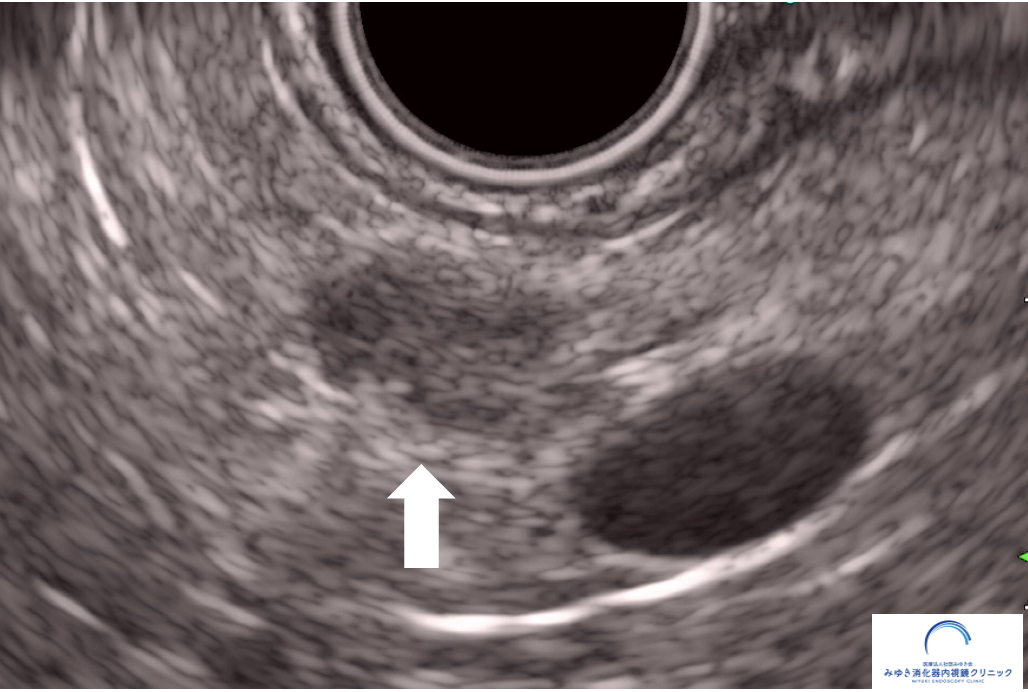

膵管拡張を指摘された場合、大切なのは「膵管がなぜ太くなっているのか」を確認することです。 腹部エコーやCT、MRI/MRCPで膵管の拡張が分かっても、 その原因となる小さな病変までははっきりしないことがあります。

超音波内視鏡(EUS)は、胃や十二指腸の中から膵臓の近くに超音波をあてて観察する検査です。 体の外から行う腹部エコーと比べて膵臓に近い位置から観察できるため、 膵管の狭くなっている部分や、CT・MRIでは分かりにくい小さな病変の評価に役立つことがあります。

他院の腹部エコーおよびCTで膵管拡張を指摘され、当院で超音波内視鏡(EUS)による精密検査を行いました。

他院の腹部エコーおよびCTで膵管拡張を指摘され、当院で超音波内視鏡(EUS)による精密検査を行いました。 膵臓に約8mmの腫瘍を認め、手術の結果、ステージ1の膵がんと診断されました。 通常の検査では見つかりにくい小さな病変が、EUSによって早期発見につながった症例です。

このように、通常の検査では見つかりにくい小さな膵がんも、EUSによって発見できることがあります。